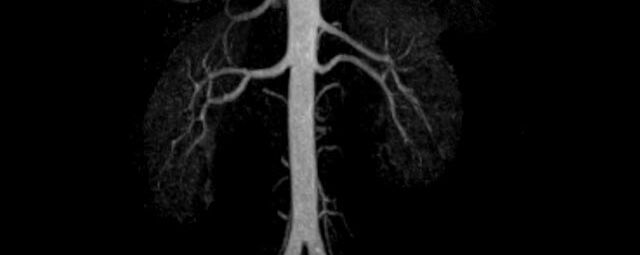

Aorta

• Bauchgefäße

• Erfassung und Verlaufskontrolle bei arteriellen Aneurysmen (Aussackungen der Arterien), vor allem der Bauchaorta

• Darstellung von Gefäßengen an Nierenarterien, Baucharterien und Becken-/Beinarterien

MR-Angiografie (MRA)

Angiographie ohne Kontrastmittel

• MR-Angiografie ohne Kontrastmittel

• Time of Flight (TOF)-Angiographie

• Phasenkontrastangiographie (PCA). Geeignet zur Quantifizierung Stenose-/Insuffizienzgrad z.B. bei Herzklappen, falls echokardiographisch die Untersuchungsbedingungen eingeschränkt sind.

Je nach Fragestellung und Körperregion Gefäßdarstellung ohne Kontrastmittel bei Kontrastmittelunverträglichkeit oder terminaler Niereninsuffizienz möglich.

Ganzkörper Angiographie mit Kontrastmittel

• MR-Angiographie mit Kontrastmittel

• Erfassung arterieller und venöser Gefäße/Bypässe aller Körperregionen mit 3D-Rekonstruktion

• je nach klinischer Fragestellung zeitaufgelöste MR-Angiographie (4D-MRA) z.B. bei Frage arteriovenöse Fistel/ Shunt oder Darstellung Unterschenkelarterien vor geplanter Bypassoperation.